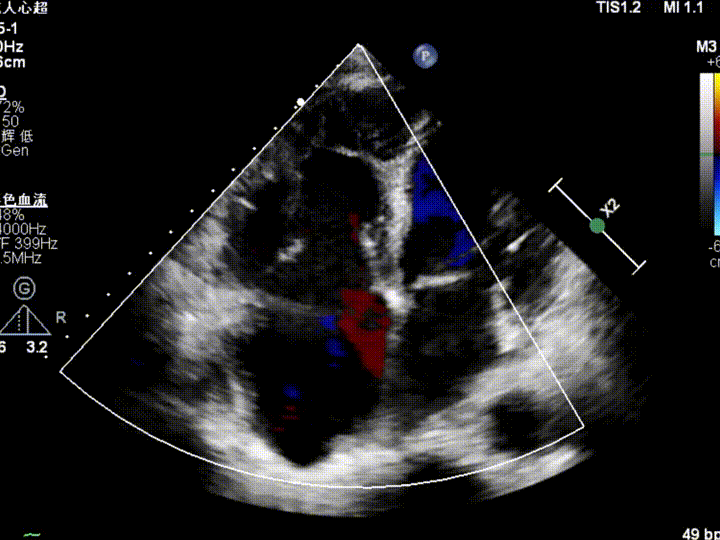

术前TTE评估:三尖瓣功能性反流,反流程度6+(巨量反流),EROA为1.24cm²,缩流颈宽度VC(平均值)为1.40cm,TAPSE为22cm,LVEF(%)为65%,三尖瓣反流量128ml,反流束来源于中部。右心、左房增大,肺动脉高压,主动脉瓣反流1+,二尖瓣反流1+。

图1 术前心超影像